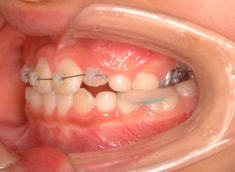

小児期ケース:反対咬合(受け口)

治療法:上顎拡大装置+フルパッシブブラケット(クリアスナップ)+フェイスマスク等

治療期間:1年3ヶ月

治療開始から6ヶ月後